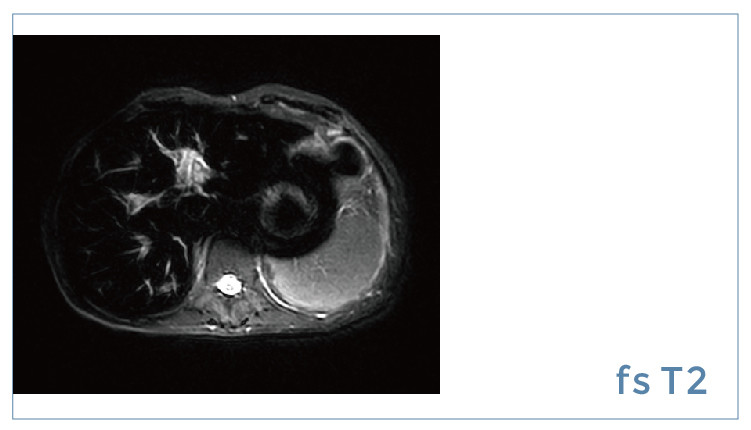

【朗润影像档案】磁共振影像病例分享(编号20190914)